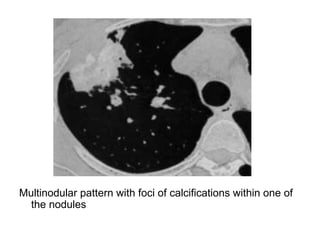

Multinodular pattern with foci of calcifications within one of

the nodules

Multinodular pattern with cavitation of some nodules